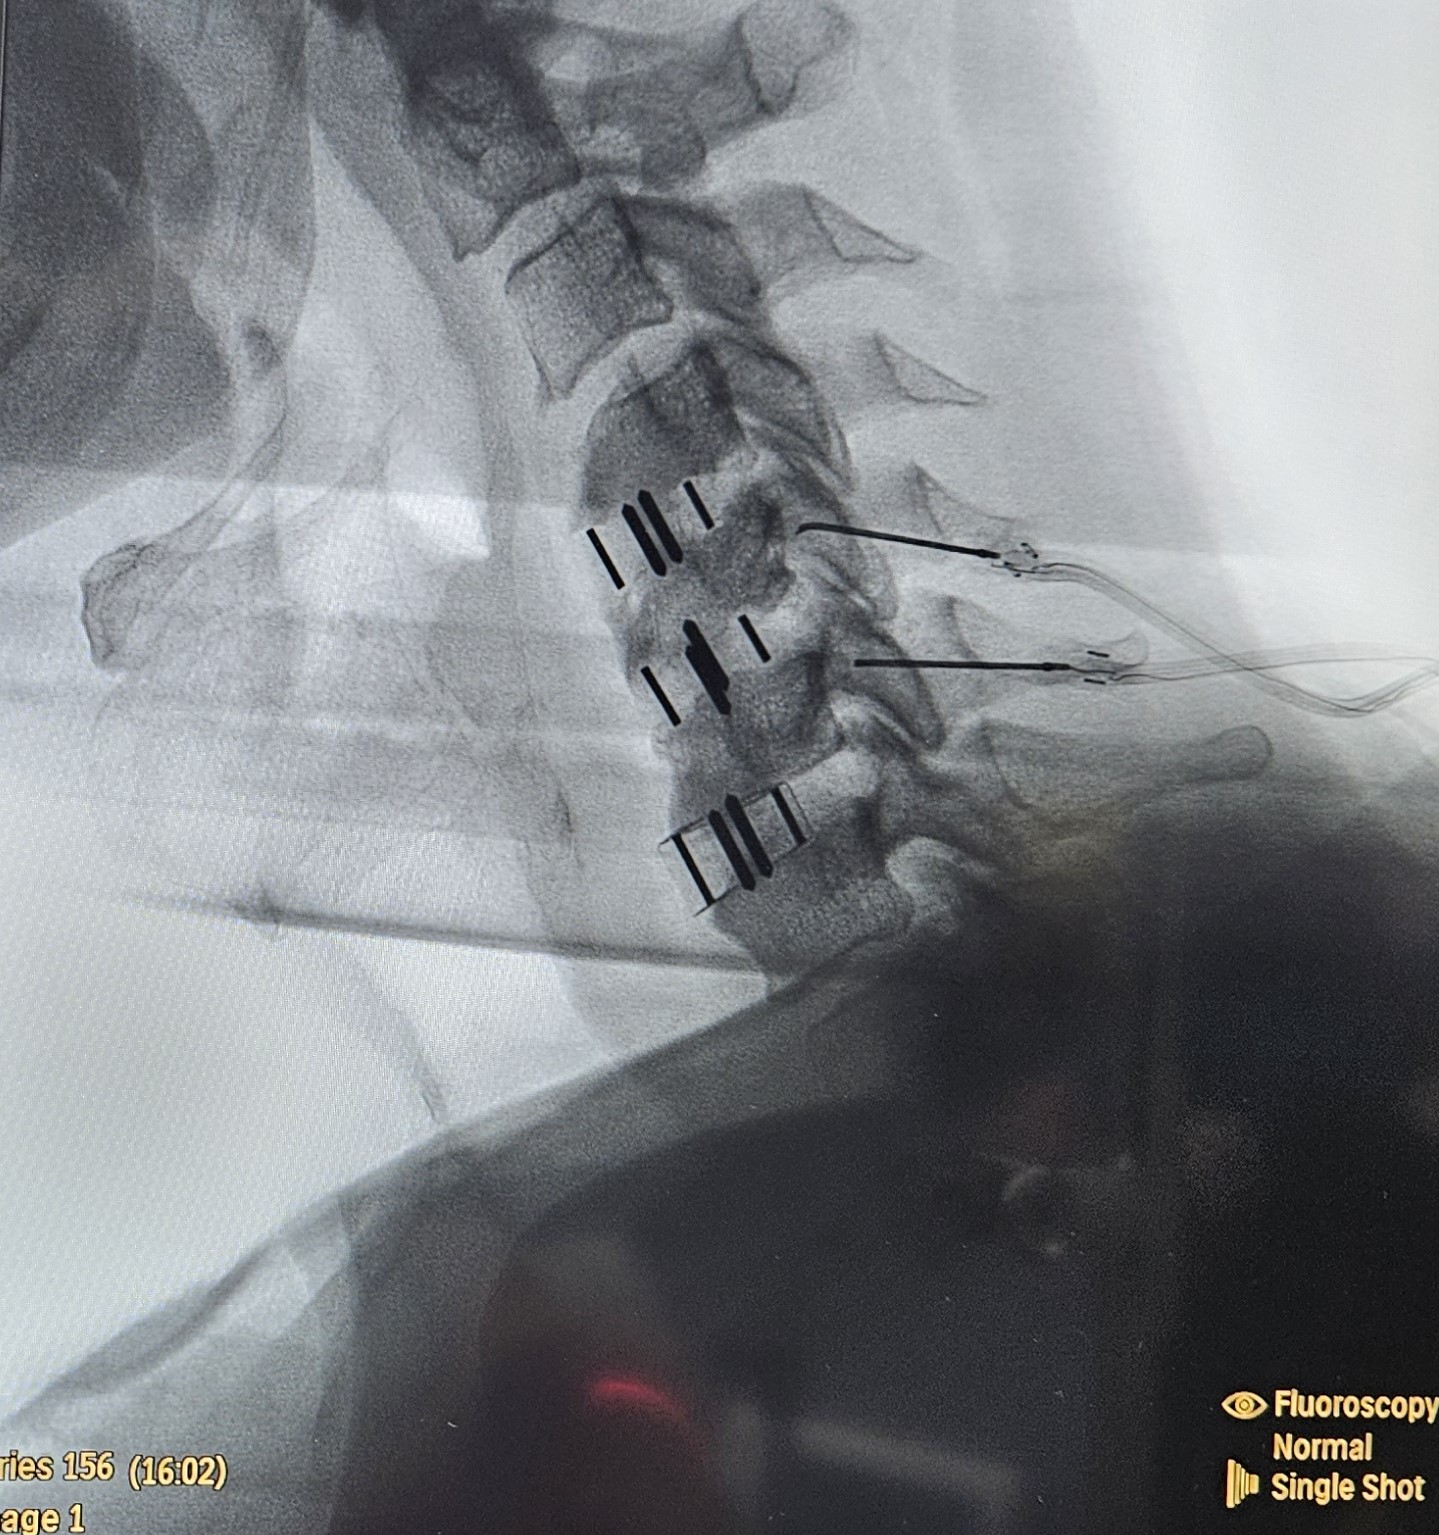

- Κατάλυση των αυχενικών αρθρώσεων με χρήση ραδιοσυχνοτήτων

- Επισκληρίδια έγχυση επί υποκείμενης κήλης μεσοσπονδυλίου δίσκου με ή χωρίς ριζιτική προσβολή

- Χειρουργική παρέμβαση επί επίμονου ριζιτικού πόνου, αδυναμίας άνω άκρων ή επί ανάπτυξης μυελοπάθειας